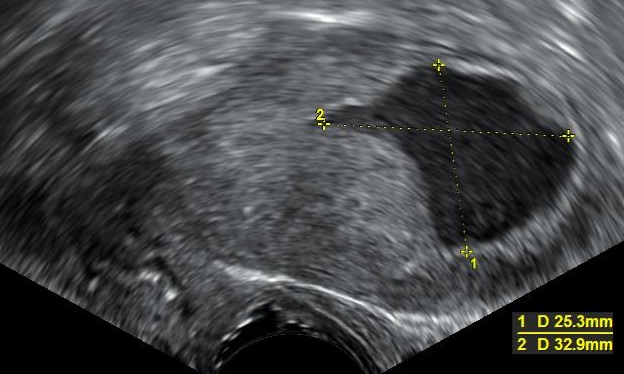

- Ultrason: Rahimdeki sıvı birikimini tespit etmek için en yaygın kullanılan yöntemdir. Transvajinal ultrason, rahim iç yapısını detaylı bir şekilde incelemeyi sağlar.

Rahimde sıvı birikmesi teşhisi, genellikle jinekolojik muayene ve görüntüleme yöntemleriyle konulur. Bir jinekolog, hastanın şikayetlerini dinledikten sonra fiziksel bir muayene yapar. Ancak kesin teşhis için aşağıdaki yöntemler sıklıkla kullanılır: